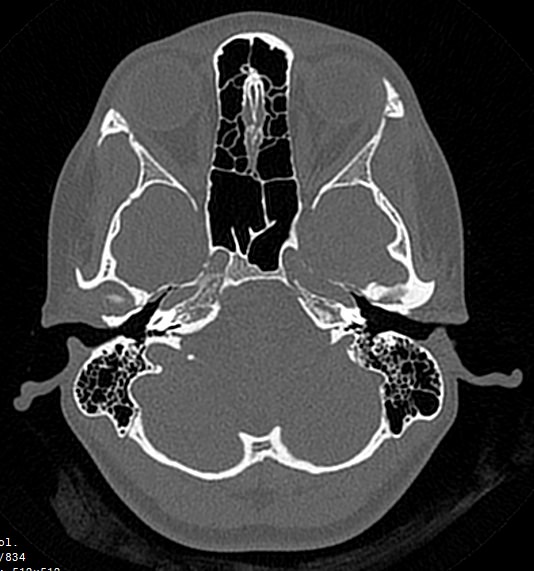

Основание черепа имеет сложное строение. Оно образовано лобными костями, решетчатой и клиновидной костью, височными и затылочными костями. На внутренней поверхности основания черепа лежат структуры ствола мозга, такие как средний мозг, Варолиев мост и продолговатый мозг, переходящий в спинной мозг на уровне большого затылочного отверстия. Поверхность основания черепа имеет многочисленные отверстия, через которые проходят черепно-мозговые нервы и сосуды головного мозга.

Наиболее информативным методом диагностики различных заболеваний в области основания черепа является мультиспиральная компьютерная томография. Исследование проводится с целью оценки травматических повреждений, диагностики аномалий развития костных структур, при планировании оперативных вмешательств, а также выявления воспалительных заболеваний и опухолевых процессов. Также на данном уровне может дифференцироваться аномалия Арнольда-Киари, заключающаяся в эктопии (то есть опущении) миндалин мозжечка различной степени выраженности.

В медицинских центрах «Доступная медицина» установлены новейшие мультиспиральные 64- и 128-срезовый компьютерные томографы экспертного уровня. В результате послойного сканирования с минимальным шагом от 0,5 мм получаются детальные изображения костных структур и прилегающих окружающих тканей. Благодаря инновационным возможностям аппаратов полученные при сканировании данные трансформируются в пространственные модели исследуемой области, которые можно увеличить, повернуть в разные стороны, рассмотреть все структуры в мельчайших подробностях. Новейшее оборудование позволяет проводить точную и достоверную диагностику заболеваний такой труднодоступной области как основание черепа. При этом современные аппараты оказывают минимальное лучевое воздействие на пациента.